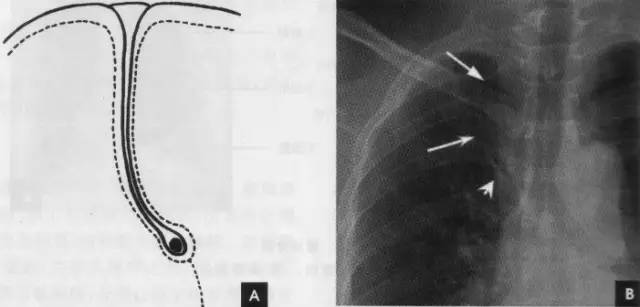

(1)奇叶系因奇静脉位置异常所致,发生率约为0.5%。胚胎发育早期,奇静脉跨于右肺尖,在肺曩上发育时,奇静脉应下移至肺尖内侧,最后固定于右侧纵隔内肺根上方。若这种滑移动作受阻,奇静脉即嵌入右肺上叶肺尖部,壁胸膜和脏胸膜也随之陷入,所以奇副裂由四层胸膜所组成,即两壁胸膜和脏胸膜,被奇静脉分隔的右肺上叶内侧部分称为奇叶。后前位胸片上,奇副裂呈细线状影,由右肺尖部向内、下走行至肺门上方,终端呈一倒置的逗点状,是奇静脉断面的垂直投影(如下图):

2、侧位肺门 侧位胸片上,两饲肺门阴影大部分重叠,若以侧位气管轴线为界,右肺门略信其前下,左肺门大部分在其后上。侧位肺门影前缘为右上肺静脉干形成的椭圆形阴影,前后径为2cm左右;中间纵行透亮区为气管及气管分叉,其内圆形透亮影表示支气管开口,右侧在上,左侧居下;后上缘为左肺动脉弓,下缘由两下肺动脉构成下行的树枝状影。因此,侧位肺门影似一尾巴拖长的“逗号”(如上右图):